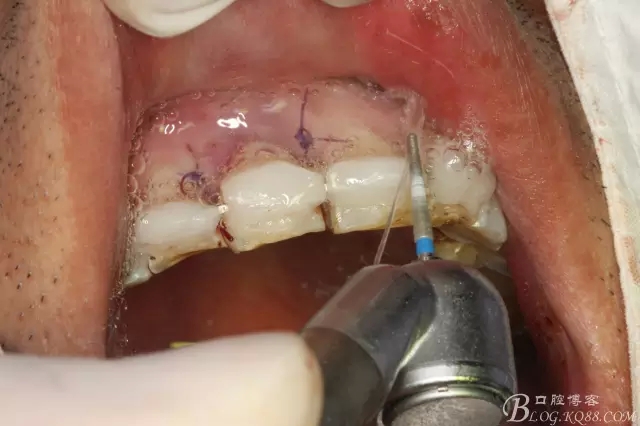

圖8.預(yù)備11根尖3mm。并MTA倒充填